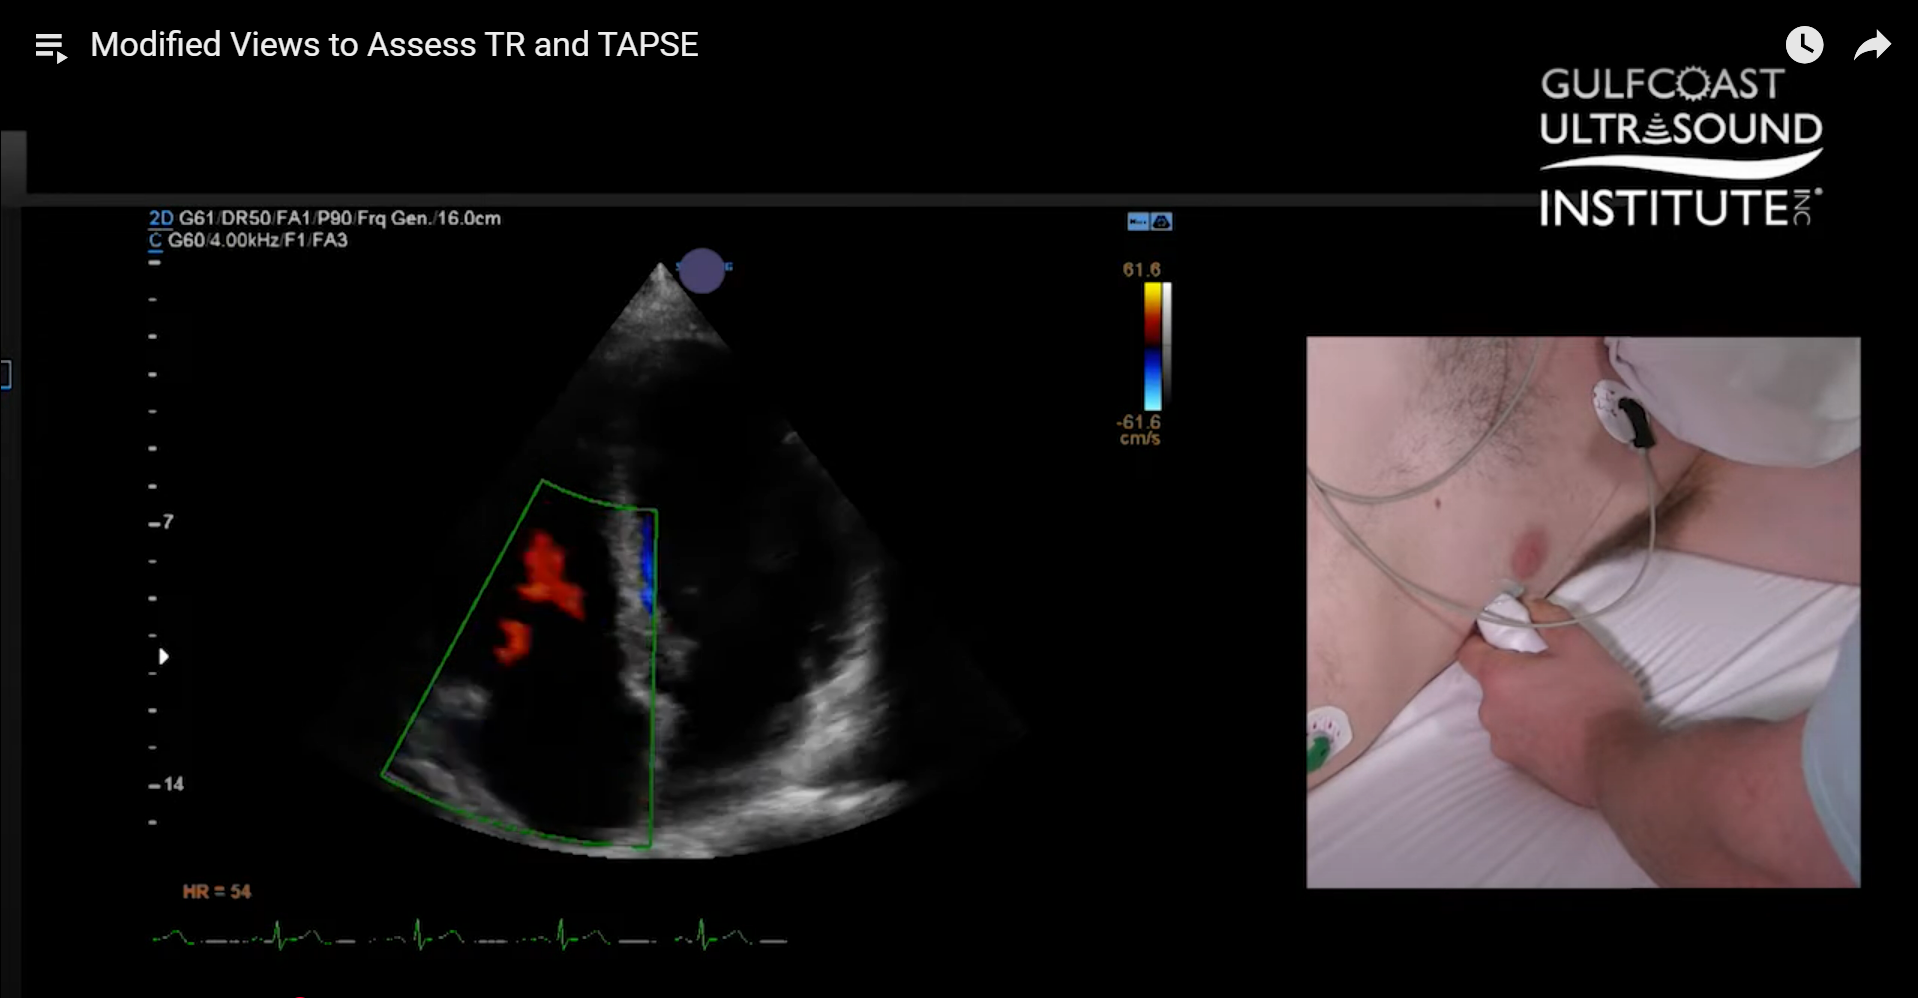

- Apply color Doppler across the tricuspid valve.

- Adding color Doppler reveals hidden TR jets that may not be visible in a standard view.

- Position the CW Doppler cursor directly at the jet’s insertion point to optimize alignment.

- This adjustment allows for a measurable TR jet that might otherwise be missed.